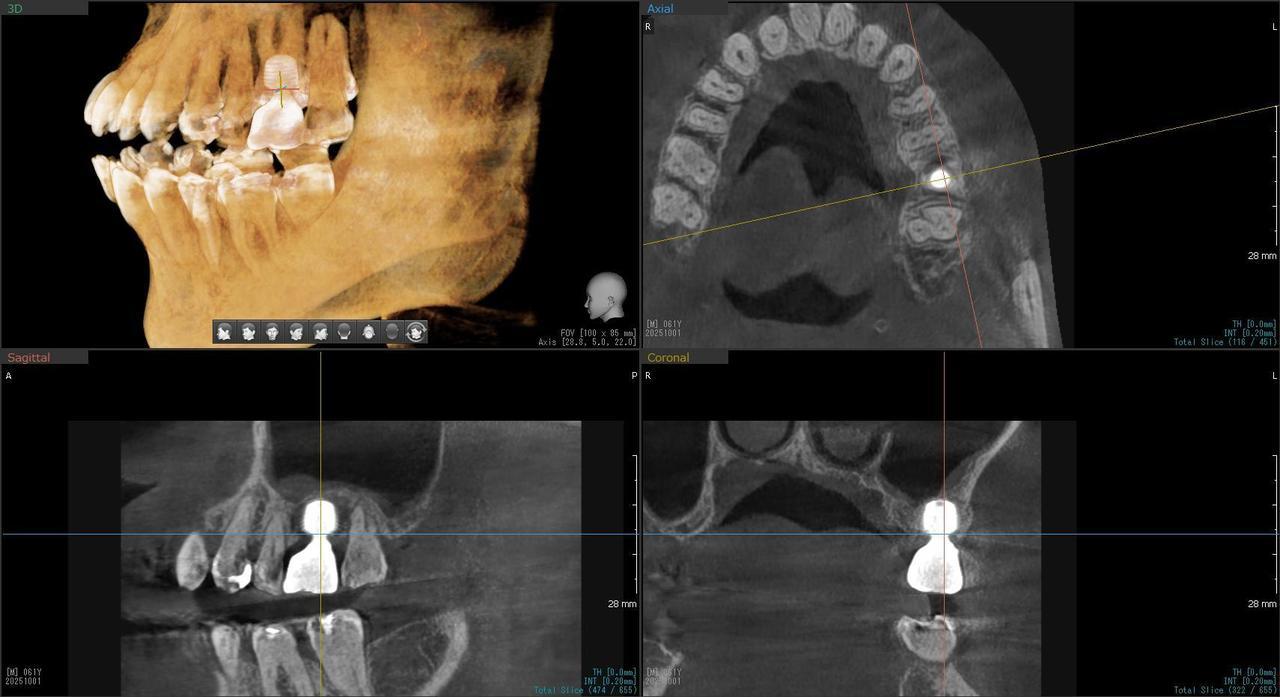

2.右上6番の上顎既存骨2mmのグラフトレスサイナスリフト(骨補填剤を使わない上顎洞挙上術)のケース

K・Y 様 女性 50代

症状としては、右上6番の歯が歯周病のため、自然に抜けてしまった。

治療法としては、歯周病により、右側6番の上顎骨が吸収して、2mm程度の骨しか残っていなかったため、サイナスリフトが必要であった。通常のサイナスリフトだと時間(時間的には1年から1年半程度かかると考えます。)と費用がかかり、患者様への時間的、肉体的、金銭的負担が大きくなることを考慮して、今回は、インプラントの種類としては、エクストラワイドショートインプラント、術式としては、デンサーバーを使用したグラフトレスサイナスリフトを選択しました。最終補綴物はジルコニアで仕上げています。

結果としては、高度に吸収した上顎骨に対するインプラント治療であったが、グラフトレスサイナスリフトを行うことで、短時間(2か月半程度)で治療を終えることができた。また、サイナスリフトによくある術後合併症である上顎洞炎を起こすことなく、患者様への肉体的な負担を抑えた治療を行うことができた。また、上顎右側6番にインプラント治療できたことにより、咬合が安定するとともに、歯周病にり患している上顎の他の歯に対する負担を少なくすることができた。

治療の期間・回数:約2か月半、6回

治療の価格:363,000円(税込)